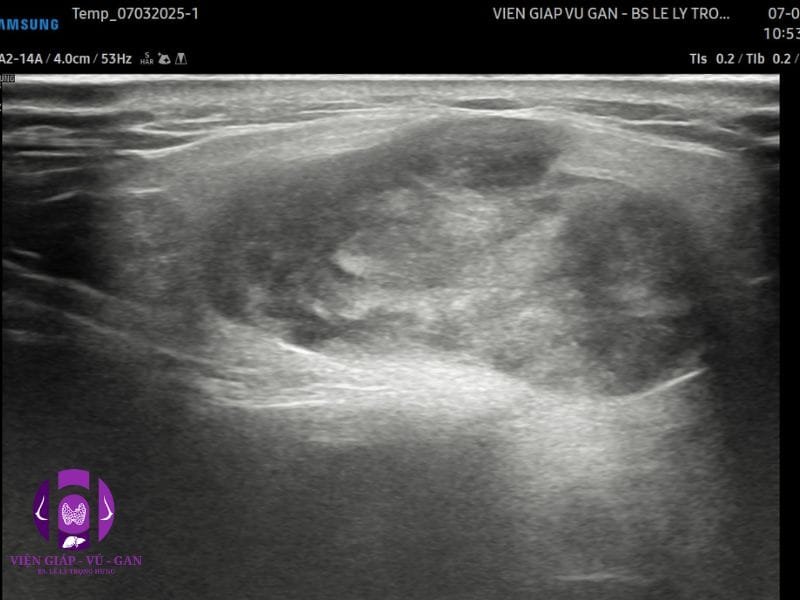

SIÊU ÂM (Máy Samsung V8) : Tuyến mang tai hai bên,

- Bên trái, thùy nông, ⅔ trên có cấu trúc echo kém không đồng nhất, bờ đa cung, tăng âm phía sau nhẹ, tăng sinh mạch máu ít.

Kết luận: Tổn thương tuyến mang tai trái nghĩ bướu hỗn hợp

- ĐẶC ĐIỂM HÌNH ẢNH

- Trên tất cả các phương tiện hình ảnh, bướu hỗn hợp thường xuất hiện dưới dạng khối tròn có ranh giới rõ ràng, “hình quả trám” hoặc “đa thùy” (nhiều gợn sóng nhỏ, nhưng không thực sự chia thùy). Chúng thường nằm ở thùy nông tuyến mang tai.